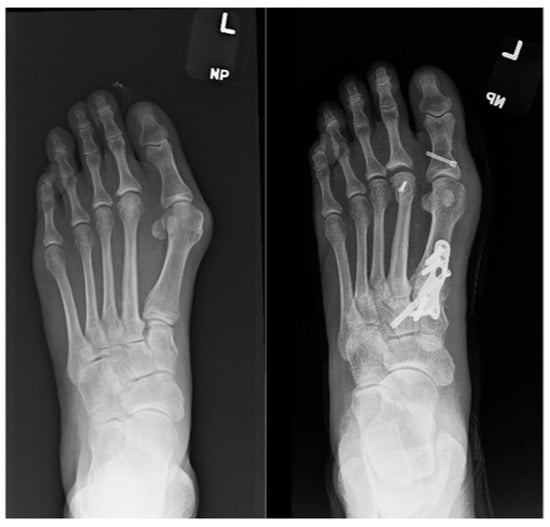

Outcomes of Lapidus Procedure Without Focused Frontal Plane Rotation of the First Metatarsal

J. Am. Podiatr. Med. Assoc. 2026, 116(3), 22; https://doi.org/10.3390/japma116030022 - 23 Apr 2026

Background: We present a retrospective radiographic analysis showcasing the ability to correct hallux valgus using the Lapidus arthrodesis without focused frontal plane rotation of the first metatarsal. Methods: A total of 33 feet in 30 patients who had undergone Lapidus arthrodesis

Background: We present a retrospective radiographic analysis showcasing the ability to correct hallux valgus using the Lapidus arthrodesis without focused frontal plane rotation of the first metatarsal. Methods: A total of 33 feet in 30 patients who had undergone Lapidus arthrodesis for the treatment of hallux abducto valgus deformity from 1 August 2015 to 31 December 2020 were identified. The median age of the cohort was 55.4 years (range, 33–78 years), 23 were female (76.7%), three (10%) underwent bilateral Lapidus arthrodesis, and the median duration of follow-up was 15.9 months (range, 5–72 months). Results: The median (minimum, maximum) preoperative first intermetatarsal angle was 16° (13°, 28°), and at final follow-up it was 5° (0°, 6°) (p < 0.001). The median (minimum, maximum) preoperative hallux abductus angle was 37° (26°, 51°), and at final follow-up it was 8.5° (0°, 22.5°) (p < 0.001). The median (minimum, maximum) preoperative tibial sesamoid position was 6 (4, 7), and at final follow-up it was 3 (2, 5) (p = 0.001). Conclusions: We found the radiographic first metatarsal lateral round sign to be ambiguous. Qualitative comparison of the results of this investigation with prior studies describing outcomes following Lapidus arthrodesis with focused frontal plane rotation of the first metatarsal suggests that similar outcomes can be achieved without employment of a decisive frontal plane rotation of the first metatarsal. Our findings lead us to believe that correction of substantial hallux abducto valgus deformities can be accomplished using the Lapidus procedure combined with lateral release of the first metatarsophalangeal joint without focused derotation of the first metatarsal.